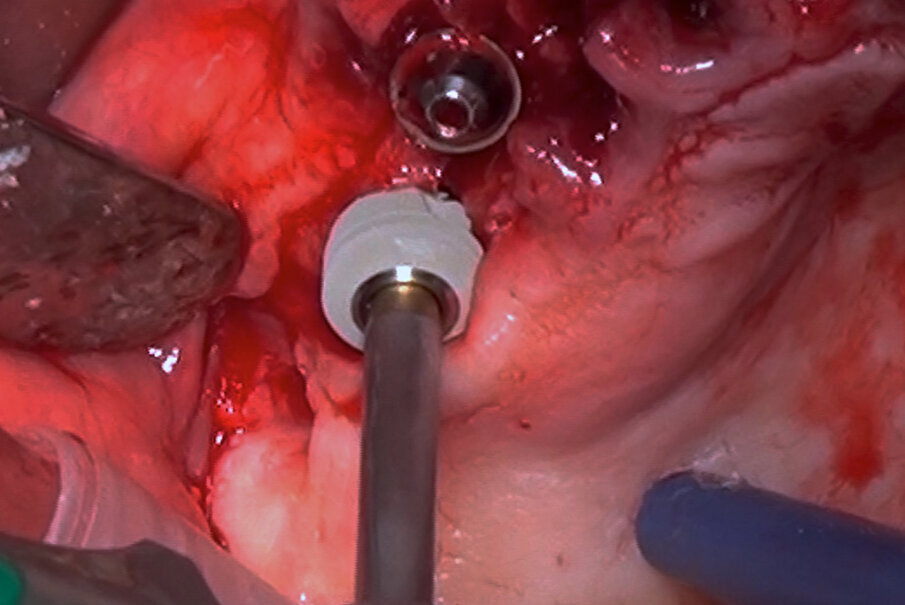

A questo punto, l’intervento si concentra sull’arcata mascellare dove viene scollato un lembo, a spessore totale, lungo tutta la lunghezza dell’arcata. Si esegue, quindi, una scrupolosa rimozione di tutti i residui di tessuto infiammato e fibroso fino ad esporre tutti i difetti ossei presenti. Successivamente, i difetti più ridotti e superficiali vengono rimodellati, come già a livello mandibolare, utilizzando il manipolo dritto sotto abbondante irrigazione. I difetti più profondi, al contrario, vengono riempiti utilizzando un xenoinnesto di origine bovina (Bio-Oss, Geistlich) ricoperto con una membrana riassorbibile in collagene suino (Bio-Gide, Geistlich). Nelle aree anteriori vengono posizionati tre impianti di lunghezza standard (blueSKY, bredent medical), mentre a livello dei primi molari vengono inserite due fixture ultra-short con diametro di 6 mm e lunghezza di 5.2 mm (copaSKY ultra short, bredent medical)

(Fig. 5). Allo scopo di ottimizzarne il livello di stabilità primaria, particolare attenzione viene posta nella ricerca di un bi-corticalismo creando una frattura a legno verde, mediante l’utilizzo di osteotomi di Summers, del pavimento del seno mascellare e ingaggiando la corticale del pavimento con le prime spire dell’impianto. Nessuna procedura di rialzo sinusale è stata eseguita e non si è determinata alcuna protrusione dell’impianto all’interno dei seni mascellari. Tutti gli impianti sono stati collocati con un torque di inserimento pari o superiore a 35 Ncm. Il controllo radiografico, eseguito mediate esame ortopanoramico, evidenzia il corretto inserimento gli impianti (Fig. 6).

Fig. 5_L’inserimento a livello del mascellare dell’impianto ultra-short.